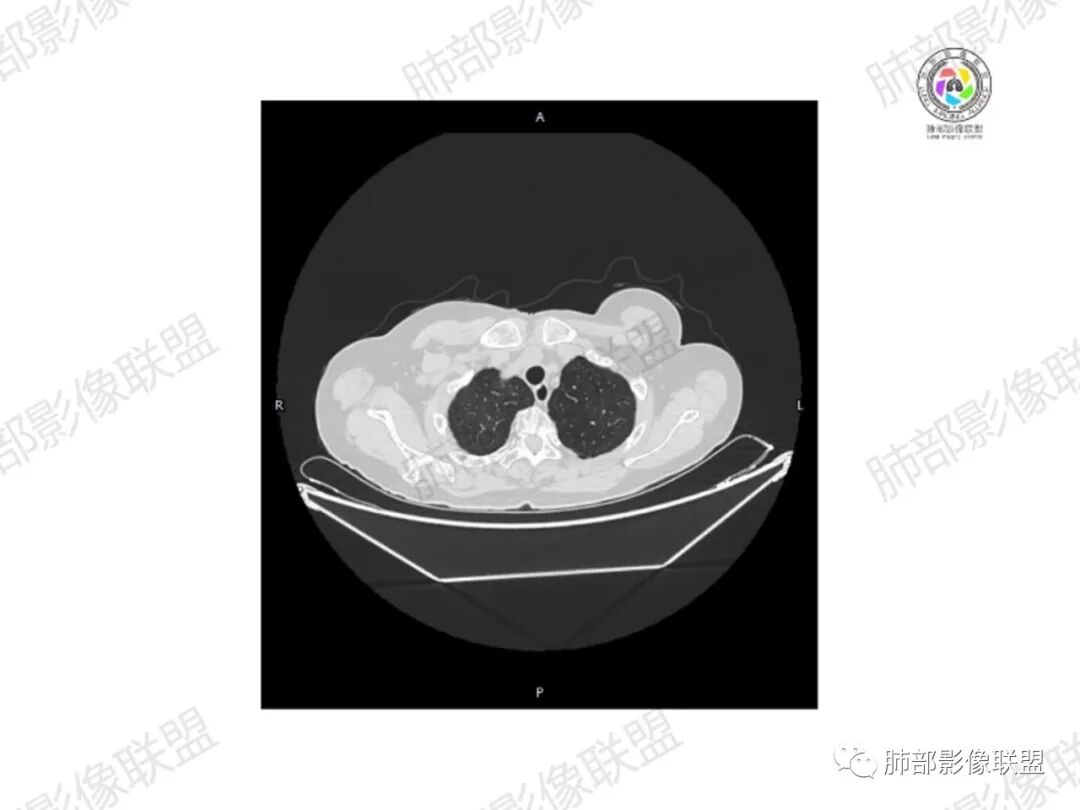

5.双肺多发类圆形结节影,边界清楚,随机分布,其间多见钙化密度影。

6.双肺门及纵隔未见肿大淋巴结。

3.双肺病灶符合转移瘤,伴有中央部分钙化者也以骨肉瘤转移较为多见。